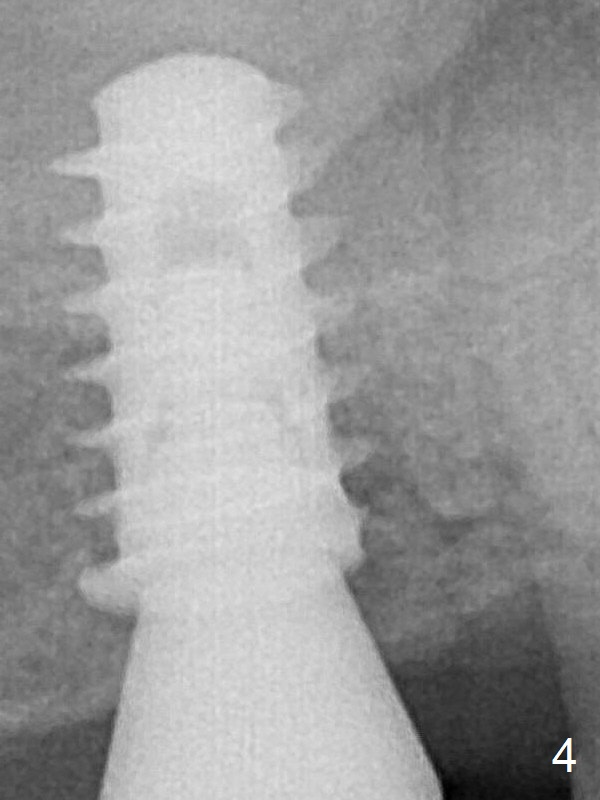

A 5.5x9 mm implant is placed evenly subcrestal (Fig.4).  The patient returns for impression 6 months postop (Fig.7).